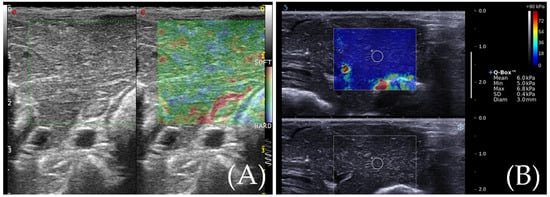

Figure 2. (A) RTE elasticity image of normal rabbit liver and the normal rabbit liver elasticity diagram show three colors: yellow, green, and red. (B) SWE elasticity image of normal rabbit liver and the normal rabbit liver elasticity diagram show an even blue color.